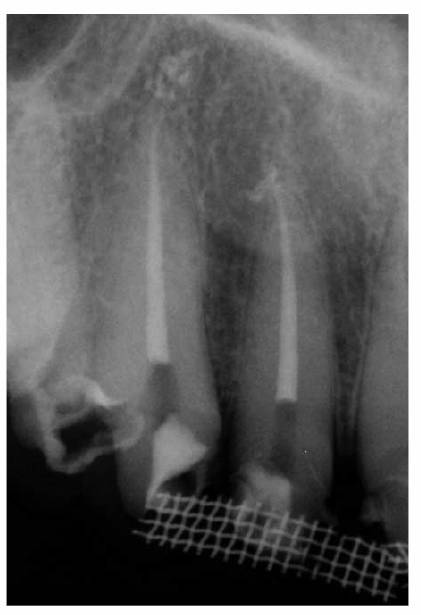

The canals should be filled completely as confirmed by radiographs. The excess

gutta-percha and root canal cement should be removed 2 to 3 mm apical to the

cervical line to prevent discoloration (Figure 19-52). In periodontally involved teeth

where longer crowns are planned, the root-filling materials should be removed

to the bone level. A 2-mm layer of white temporary stopping should be placed

over the gutta-percha.25 Remnants of the cement may be removed with

alcohol. A tooth- colored restorative material (ie, composite resin or glass

ionomer cement) may be used to fill the rest of the canal and chamber when a

post and core are not indicated.

The coronal restoration should be placed as soon as possible after completion

of the root canal treatment if it is not placed at the time when the canals are

filled. There is now building evidence that the coronal restoration is as

important, if not more important, in microbiologically sealing the root canal

system as the root canal obturation material (Figures 19-53A

and B). In a

recent study, Ray and Trope evaluated the radiologic quality of both coronal

and canal obturations.24 It was demonstrated that a tooth with good

coronal and root seals had the best rate of absence of periapical lesions

(91.4%). Good restoration resulted in significantly less incidence of

periapical lesions than good endodontic filling (80% versus 75.7%). Poor

restoration resulted in significantly more periapical lesions than poor

endodontic fillings (48.6% versus 30.2%).

Figure 19-52: Gutta-percha root filling cut back 3 mm apical to the cervical line to prevent discoloration. Two millimeters of white temporary stopping is placed over the gutta-percha. This space will be restored with composite resin. The adjacent tooth will be restored with a crown.

Figure 19-53A and B: (A) Thirty-five years after root canal therapy. The teeth are asymptomatic, and there are no radiographic changes. (B) Three years after distobuccal root resections and new castings. Periapical lesions developed around the mesiobuccal roots. During the extended treatment phase, the coronal ends of the silvers points were periodically exposed to saliva.